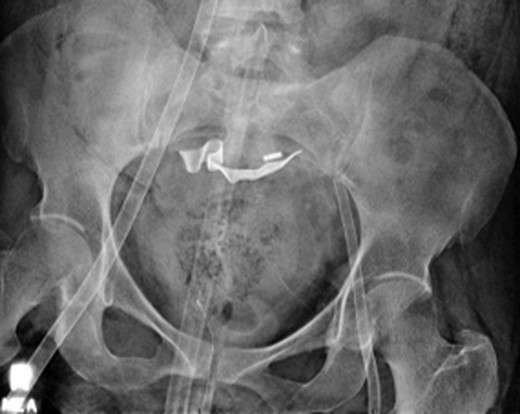

A 61-year-old female initially presented to the emergency department with shortness of breath and back pain. The patient had recently traveled to Haiti and made several trips to Denver by car. She was initially alert and oriented but sustained a cardiac arrest shortly after arrival and underwent CPR for pulseless electrical activity (PEA). Approximately 5 min into resuscitative efforts, a LUCAS 2.0 (Physio-Control Inc., Lund, Sweden) device was placed for continued chest compressions for 30 min. Bedside echocardiogram showed a dilated RV with a suspected massive PE and the ECMO team was activated. The patient was intubated and VA-ECMO access was obtained through the left femoral artery and right common femoral vein under ultrasound guidance with 17 Fr arterial and 25 Fr venous cannulas (Fig. 1). After a total of 35 min of CPR, the patient had spontaneous return of circulation.

Abdominal x-ray of VA-ECMO cannulation within the IVC and left iliac artery.